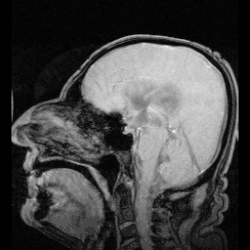

MRI showing pulsation of CSF

CSF moves in a single outward direction from the ventricles, but multidirectionally in the subarachnoid space.[6][5] The flow of cerebrospinal fluid is pulsatile, driven by the cardiac cycle.[7] The flow of CSF through perivascular spaces in the brain (surrounding the cerebral arteries) is obtained through the pumping movements of the walls of the arteries.[7]